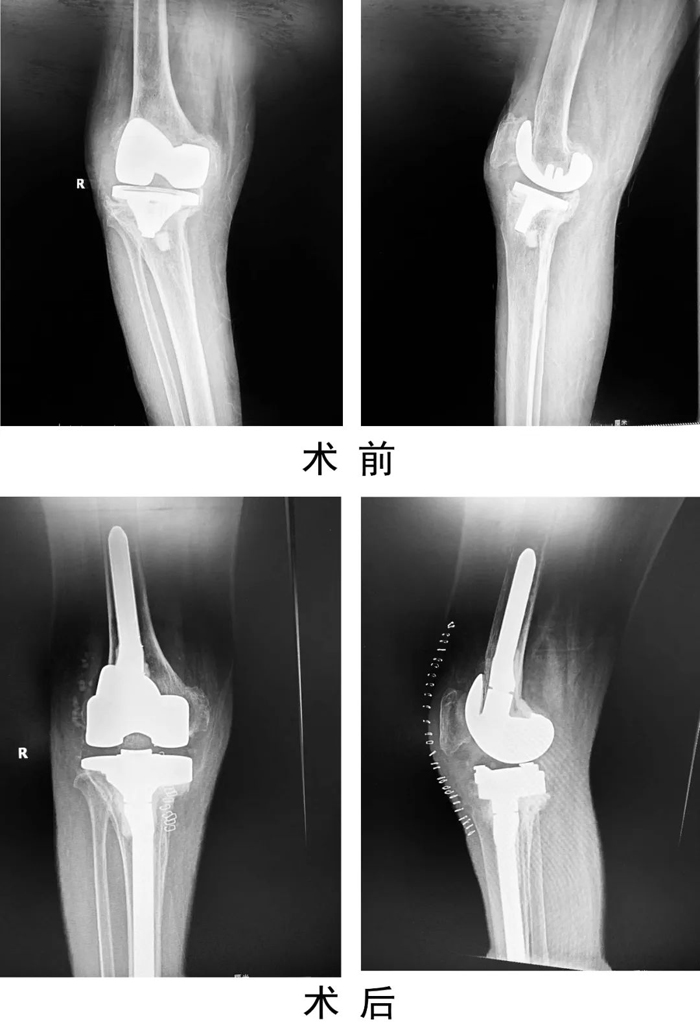

患者,女,69歲,因“右膝人工關節置換術后6年,疼痛伴活動受限1年”入住關節運動醫學二科。術前X線示右膝人工關節假體松動,感染指標檢查:C反應蛋白80mg/L,血沉20mm/h,關節穿刺培養提示表皮葡萄球菌感染。查體見有膝部有一長約15cm手術疤痕,皮溫高,關節腫脹,右膝關節活動受限。入院診斷為:右膝關節假體周圍感染,人工假體松動,右脛骨平臺骨缺損。

患者入院后,關節運動醫學二科手術團隊制定嚴密的手術計劃,為患者實施了一期右膝人工關節翻修術,一次手術清除原假體,徹底清創后,重新植入翻修假體。手術后患者右膝刀口一期愈合出院,患膝功能良好,疼痛緩解。復查感染指標C反應蛋白4.45mg/L。